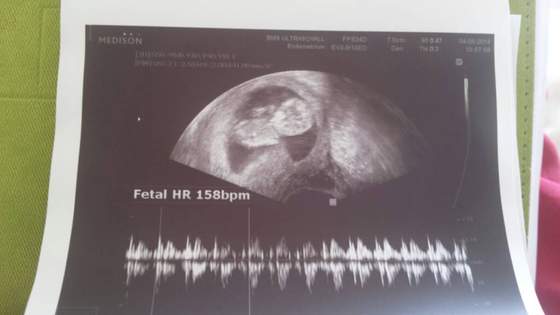

Zapomnialam napisac. Moj dzidzius ma juz 5.5 cm jest o tydzien wiekszy wg usg i tym sposobem termin porodu wychodzi mi 17.02 :-) a Prezesa rodzilam 18.02 hihi. Wszystko dobrze mis sobie spal. W przyszla srode mam prenatalne usg :-)